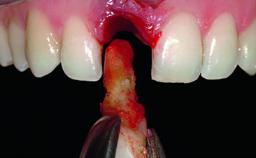

Replacement of an Ankylosed Upper Left Central Incisor: Bone Augmentation and Socket Grafting, Late Placement of an RC Bone Level Implant

A 15-year-old male patient was referred to us by his pediatric dentist in June 2004 for evaluation of treatment options for his failing tooth 21. The patient had recently seen an endodontist for internal bleaching and been advised that there had been significant resorption and ankylosis. The patient’s mother was concerned because the tooth appeared shorter than the adjacent one. His past dental history was significant for trauma (September 2001), where the tooth had been avulsed and reimplanted. Teeth 11 and 21 had been endodontically treated.

Bone Augmentation Horizontal|Simultaneous|Staged

Augmentation Materials Autogenous chips|Xenogenous

Bone Volume Deficient horizontally, requiring prior grafting